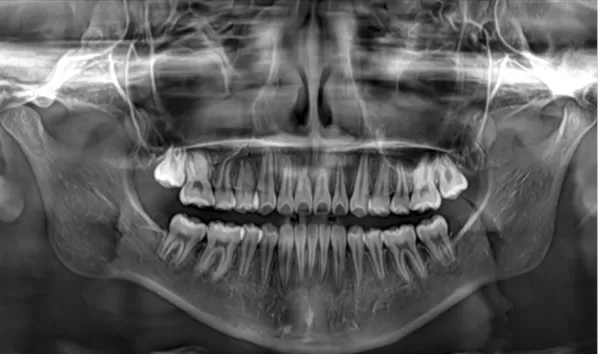

X-rays before treatment

[Panoramic Radiography/Lateral Cephalogram]